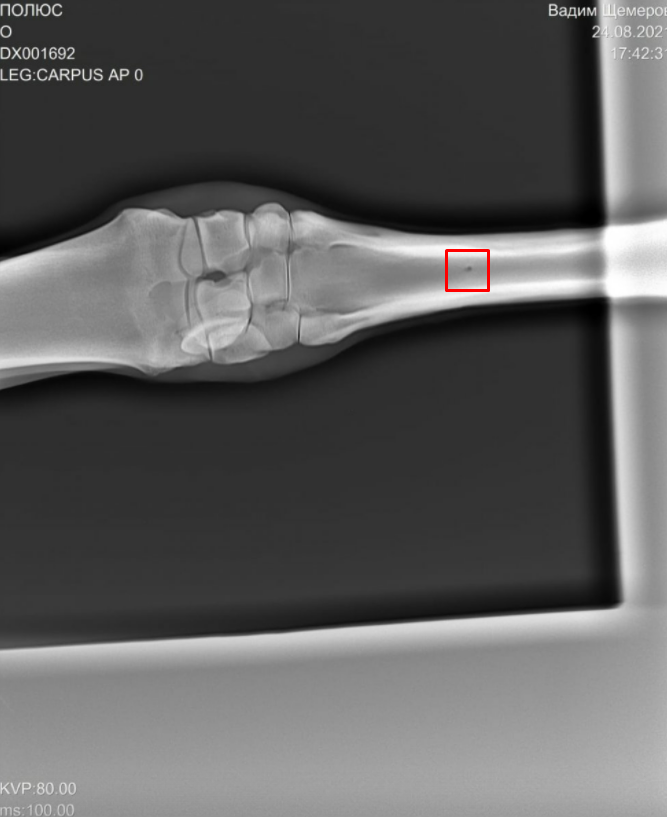

На рентгеновских снимках выявлено:

1) остеохондроз и чип в области путового сустава правой грудной конечности.